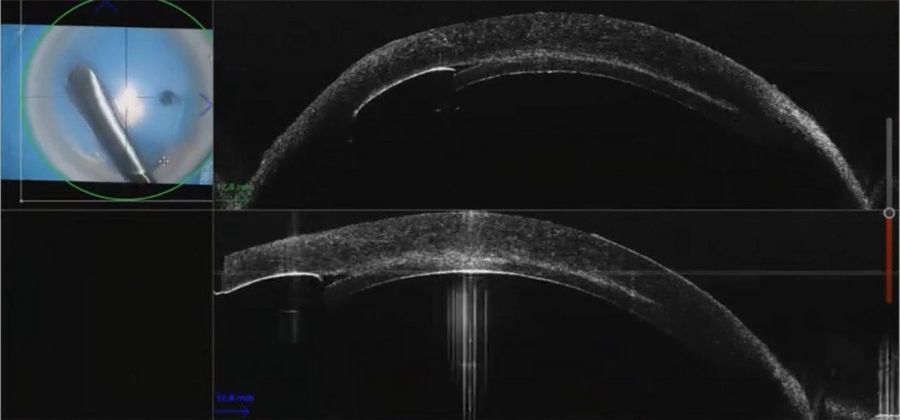

The use of intraoperative OCT can help overcome the challenges of endothelial keratoplasty through real-time information supporting decision-making. Endothelial keratoplasty is a surgical procedure to replace a damaged endothelium with healthy donor tissue, which includes both DSEK and DMEK techniques.

- Understand the role of intraoperative OCT, in particular for the successful orientation and positioning of the donor tissue in DSEK, DALK and DMEK procedures.

When performing DSEK in eyes that have had a penetrating keratoplasty or other pathologies such as posterior membrane dystrophies, it is valuable to see DM as opposed to stromal tears or folds.

When performing the strip, the intraoperative OCT provided live confirmation of where DM was present. This is particularly helpful when there is a poor view e.g. in this case of ocular trauma. The OCT showed the separation of Descemet’s membrane very clearly.